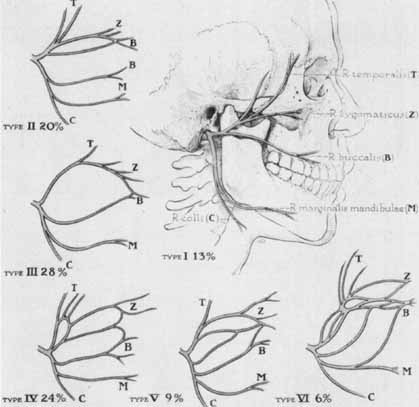

of 350 cervical facial halves. Surg Gynecol Obstet 102:385, 1956 13. Nager GT, Nager N: The arteries of the human middle ear, with particular regard to the blood